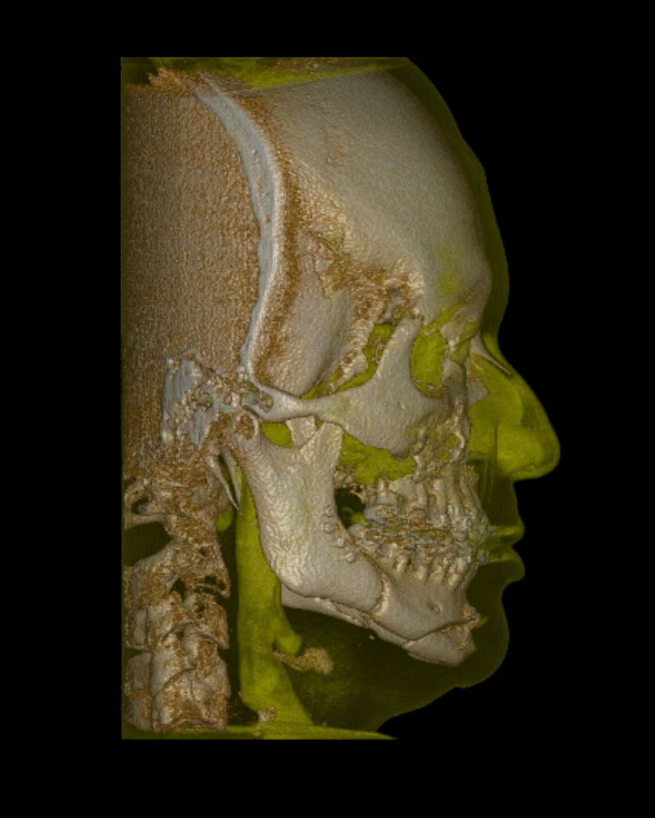

TC de face (do Hióide à Glabela), reconstrução 3D do tecido ósseo, radiografia panorâmica, telerradiografia lateral com traçado, cortes transversais e axial de maxila e mandíbula e arquivo DICOM- entregue em pasta de Pvc.

TC de face (do Hióide à Glabela), reconstrução 3D do tecido ósseo, radiografia panorâmica, telerradiografia lateral e frontal com traçado, cortes transversais e axial de maxila/mandíbula e arquivo DICOM – entregue em pasta de Pvc.

TC de face (do Hióide à Glabela), reconstruções 3D do tecido mole/ósseo/vias aéreas, radiografia panorâmica, telerradiografia lateral e frontal com traçado, cortes transversais e axial de maxila/mandíbula, ATM e arquivo DICOM – entregue em pasta e caixa de Pvc.